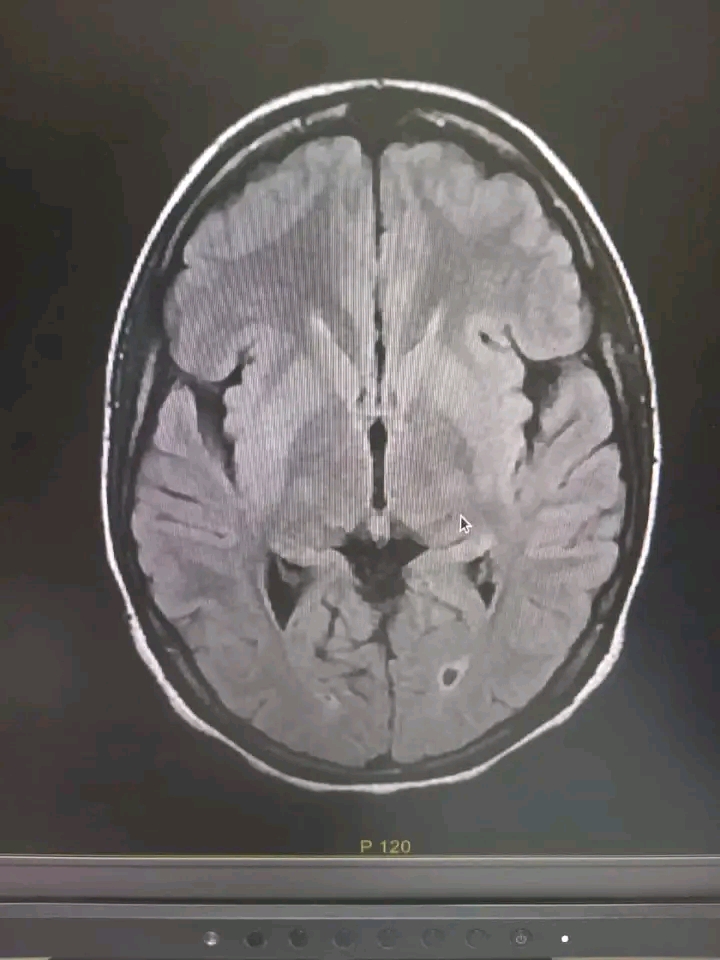

أعلن الجيش الوطني عبر صفحته على الفيسبوك، أن مختلف مستشفيات العاصمة نواكشوط، تسجل أكثر من عشرين حالة جلطة دماغية بشكل يومي.

وأوضح البيان أن هذا العدد المسجل في مستشفيات العاصمة لوحدها، يجعل الجلطات الدماغية، مشكلة من مشاكل الصحة العمومية في البلاد.

جاء ذلك في بيان نشره الجيش بعد نجاح فريق طبي في المستشفى العسكري في عملية تفتيت جلطة دماغية، لمريضة عشرينية قبل أيام.